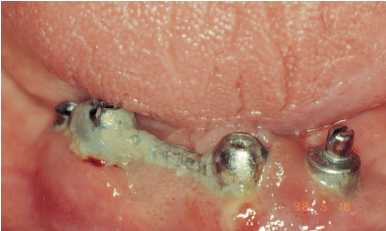

Figura 1. Paciente con acúmulo

de cálculo y placa, bolsas

periimplantarias y movilidad de

los implantes